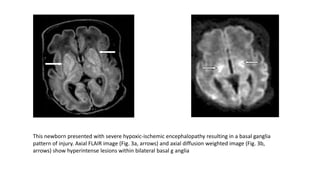

This newborn presented with severe hypoxic-ischemic encephalopathy resulting in a basal ganglia

pattern of injury. Axial FLAIR image (Fig. 3a, arrows) and axial diffusion weighted image (Fig. 3b,

arrows) show hyperintense lesions within bilateral basal g anglia